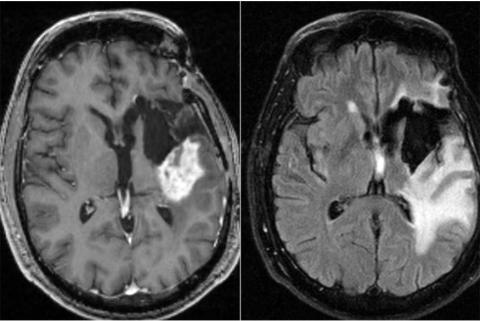

Plusieurs études ont déjà suggéré l’intérêt de la chronothérapie dans le traitement des cancers, la croissance incontrôlée des cellules cancéreuses étant souvent associées à des oncogènes qui perturbent le cycle circadien. Cette recherche d’une équipe de l'Université de Washington suggère à nouveau que le moment choisi pour la chimiothérapie pourrait influencer sur son efficacité. Ces données, présentées dans la revue Neuro-Oncology Advances sont tout particulièrement cruciales, ici pour le traitement du glioblastome, un type agressif de cancer du cerveau, à mauvais pronostic.

Le glioblastome est incurable. La survie moyenne après le diagnostic est estimée à 15 mois, avec une espérance de survie à 5 ans de moins de 10%. Alors que de nombreux essais cliniques sur de nouveaux candidats sont en cours, cette étude suggère qu'un ajustement mineur du traitement standard actuel, soit administrer la chimiothérapie le matin plutôt que le soir, pourrait déjà prolonger la survie des patients de plusieurs mois.